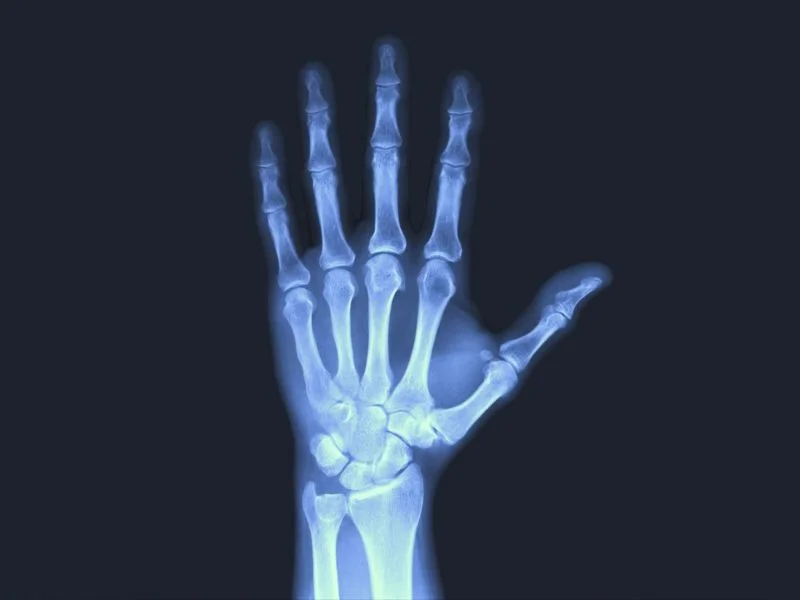

RADIOGRAFÍA DE MUÑECA

La radiografía de muñeca es un examen de diagnóstico por imagen que emplea rayos X para generar una representación detallada de las estructuras internas de la muñeca, incluidas las articulaciones y los huesos circundantes, como el radio y el cúbito.

Cuando los rayos atraviesan los tejidos del cuerpo, interactúan de manera distinta con huesos y músculos: los huesos, al ser más densos, absorben mayor cantidad de radiación y aparecen blancos en la imagen resultante, mientras que los tejidos blandos, que permiten un mayor paso de los rayos, se ven en tonos más oscuros.